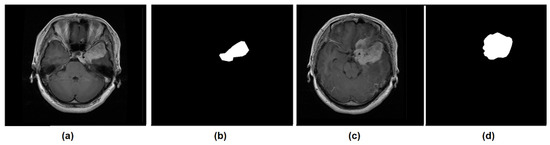

The dataset used in this study is a 2D brain tumor segmentation dataset. It is publicly available on Kaggle at the following link: https://www.kaggle.com/datasets/nikhilroxtomar/brain-tumor-segmentation/data (accessed on 20 September 2023) [44]. This dataset comprises 3064 pairs of T1-weighted contrast-enhanced images and their respective binary masks indicating tumor presence. The photos are in .png format; each image is sized 512 × 512 pixels. The dataset consists of imaging data from 233 patients, encompassing various types of brain tumors. The distribution of tumor types within the dataset is as follows: Meningioma—708 slices; Glioma—1426 slices; Pituitary tumor—930 slices. These data provide a diverse representation of brain tumor types commonly encountered in clinical practice, facilitating comprehensive research and development of segmentation algorithms and diagnostic tools [38]. Figure 2 shows an example of a brain MR image alongside its corresponding tumor segments.

Figure 2. Multiple MRI brain images depicting tumors with corresponding masks from a 2D brain tumor segmentation dataset [44]. (a) Original MRI image showing a tumor. (b) Binary mask highlighting the tumor region. (c) Additional MRI scan. (d) Corresponding binary mask indicating the tumor.